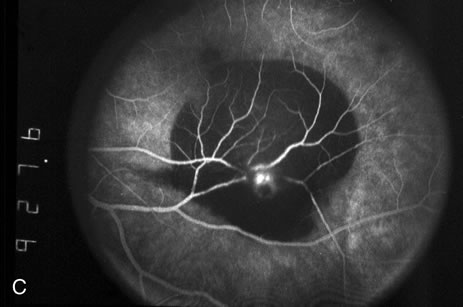

Fig. 2. A. Color fundus photograph of a 200-micron macroaneurysm that arises from a retinal artery near the optic disc with thin subretinal hemorrhage that does not threaten the fovea. B. The midphase fluorescein angiogram reveals blockage of choroidal but not retinal vascular hyperfluorescence. C. The late-phase angiogram demonstrates staining of the macroaneurysm.[pa[et[ol0]